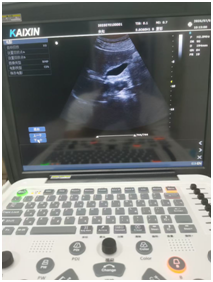

腹部B超和阴超B超 |

腹部B超和阴超(经阴道超声)都属于B超检查的范畴,在妇产科及腹部脏器检查中应用广泛,以下从多个方面为你介绍两者的情况: 一、检查方式 腹部B超:是将B超探头放在下腹部观察盆腔内情况,是一种非侵入性的检查方式。检查前需要患者适量憋尿,使膀胱适度充盈,以推开肠道气体干扰,更清晰地显示盆腔脏器。 阴超:是将探头套上一次性无菌探头套(通常是避孕套),然后缓慢放入阴道内,进行近距离的观察。检查前需排空膀胱,操作相对直接,但属于侵入性检查。 二、 优势 腹部B超:检查范围较广泛,除了可以观察子宫、附件等盆腔脏器外,还能对腹部其他脏器,如肝脏、胆囊、胰腺、脾脏、肾脏等进行检查。适合所有有检查需求的人群,包括未婚女性。 阴超:图像更清晰、分辨率更高,能更清晰地显示子宫、卵巢及盆腔的细微结构和病变,尤其对于肥胖患者或盆腔深部器官的观察效果更好。而且无需憋尿,节省时间,患者更舒适。 三、局限性 腹部B超:由于检查时探头与盆腔脏器之间隔着腹壁、膀胱等多层组织,可能会受到腹壁脂肪厚度、肠道气体等因素的干扰,对于一些较小的病变或位置较深的结构显示不如阴超清晰。此外,憋尿过程可能会让患者感到不适,且等待膀胱充盈的时间较长。 阴超:检查范围相对局限,主要用于观察盆腔内的生殖器官,对腹部其他脏器无法检查。同时,它不适合未婚女性、阴道畸形、阴道炎症急性期以及月经期的女性。 四、适用情况 腹部B超:常用于初步筛查腹部脏器的病变,如肝囊肿、胆结石、肾积水等;也适用于孕期检查,尤其是孕早期和孕晚期,可观察胎儿的发育情况、胎盘位置等。对于未婚女性的妇科检查,腹部B超是首选的检查方法。 阴超:常用于监测卵泡发育、诊断早期宫外孕、子宫肌瘤、子宫内膜病变、卵巢囊肿等妇科疾病。在辅助生殖技术中,阴超也是监测卵泡和黄体功能的重要手段。 这两种检查都是超声检查在妇产科常用的方式。腹部B超需要憋尿,使膀胱适度充盈推开肠道,以更清晰观察盆腔内器官情况,适合未婚女性、月经期女性等。阴超B超则是将探头放入阴道内进行检查,无需憋尿,图像更清晰,但不适合未婚女性、阴道出血较多者等。 即刻关注凯信微信号xzkxele,就能查看更多关于B超机、彩超机、兽用B超、宠物彩超的详情。(只需在公众号里搜;凯信超声;或扫描下方的二维码就可以加关注!)如需咨询报价信息,可联系客服热线15050003098 400-928-6626.